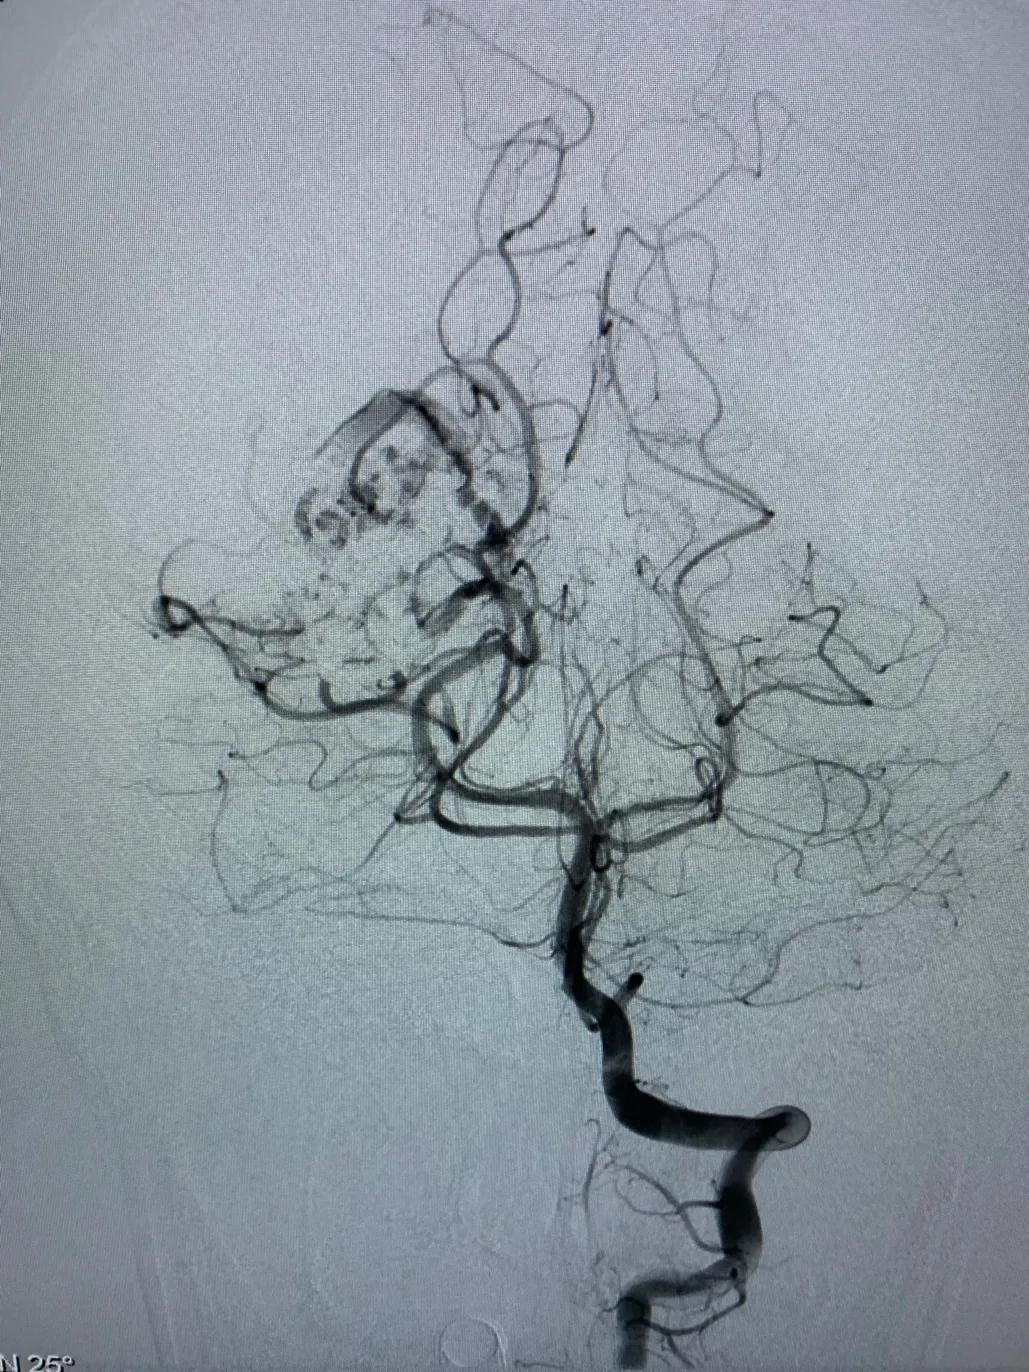

本组部分病例在使用Apollo微导管进行Onyx栓塞时,采用此种技术,可有效的阻止Onyx返流。本病例为一小女孩,右侧枕叶血管畸形,主要供血动脉为右侧大脑后动脉。